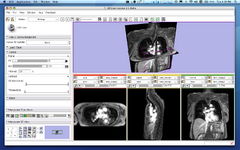

Image:B-spline-reg-detail.png|Improved: [[Modules:RegisterImages-Documentation-3.6|Expert Automated Registration]] (Casey Goodlett) | Image:B-spline-reg-detail.png|Improved: [[Modules:RegisterImages-Documentation-3.6|Expert Automated Registration]] (Casey Goodlett) | ||

Improved: Expert Automated Registration (Casey Goodlett)